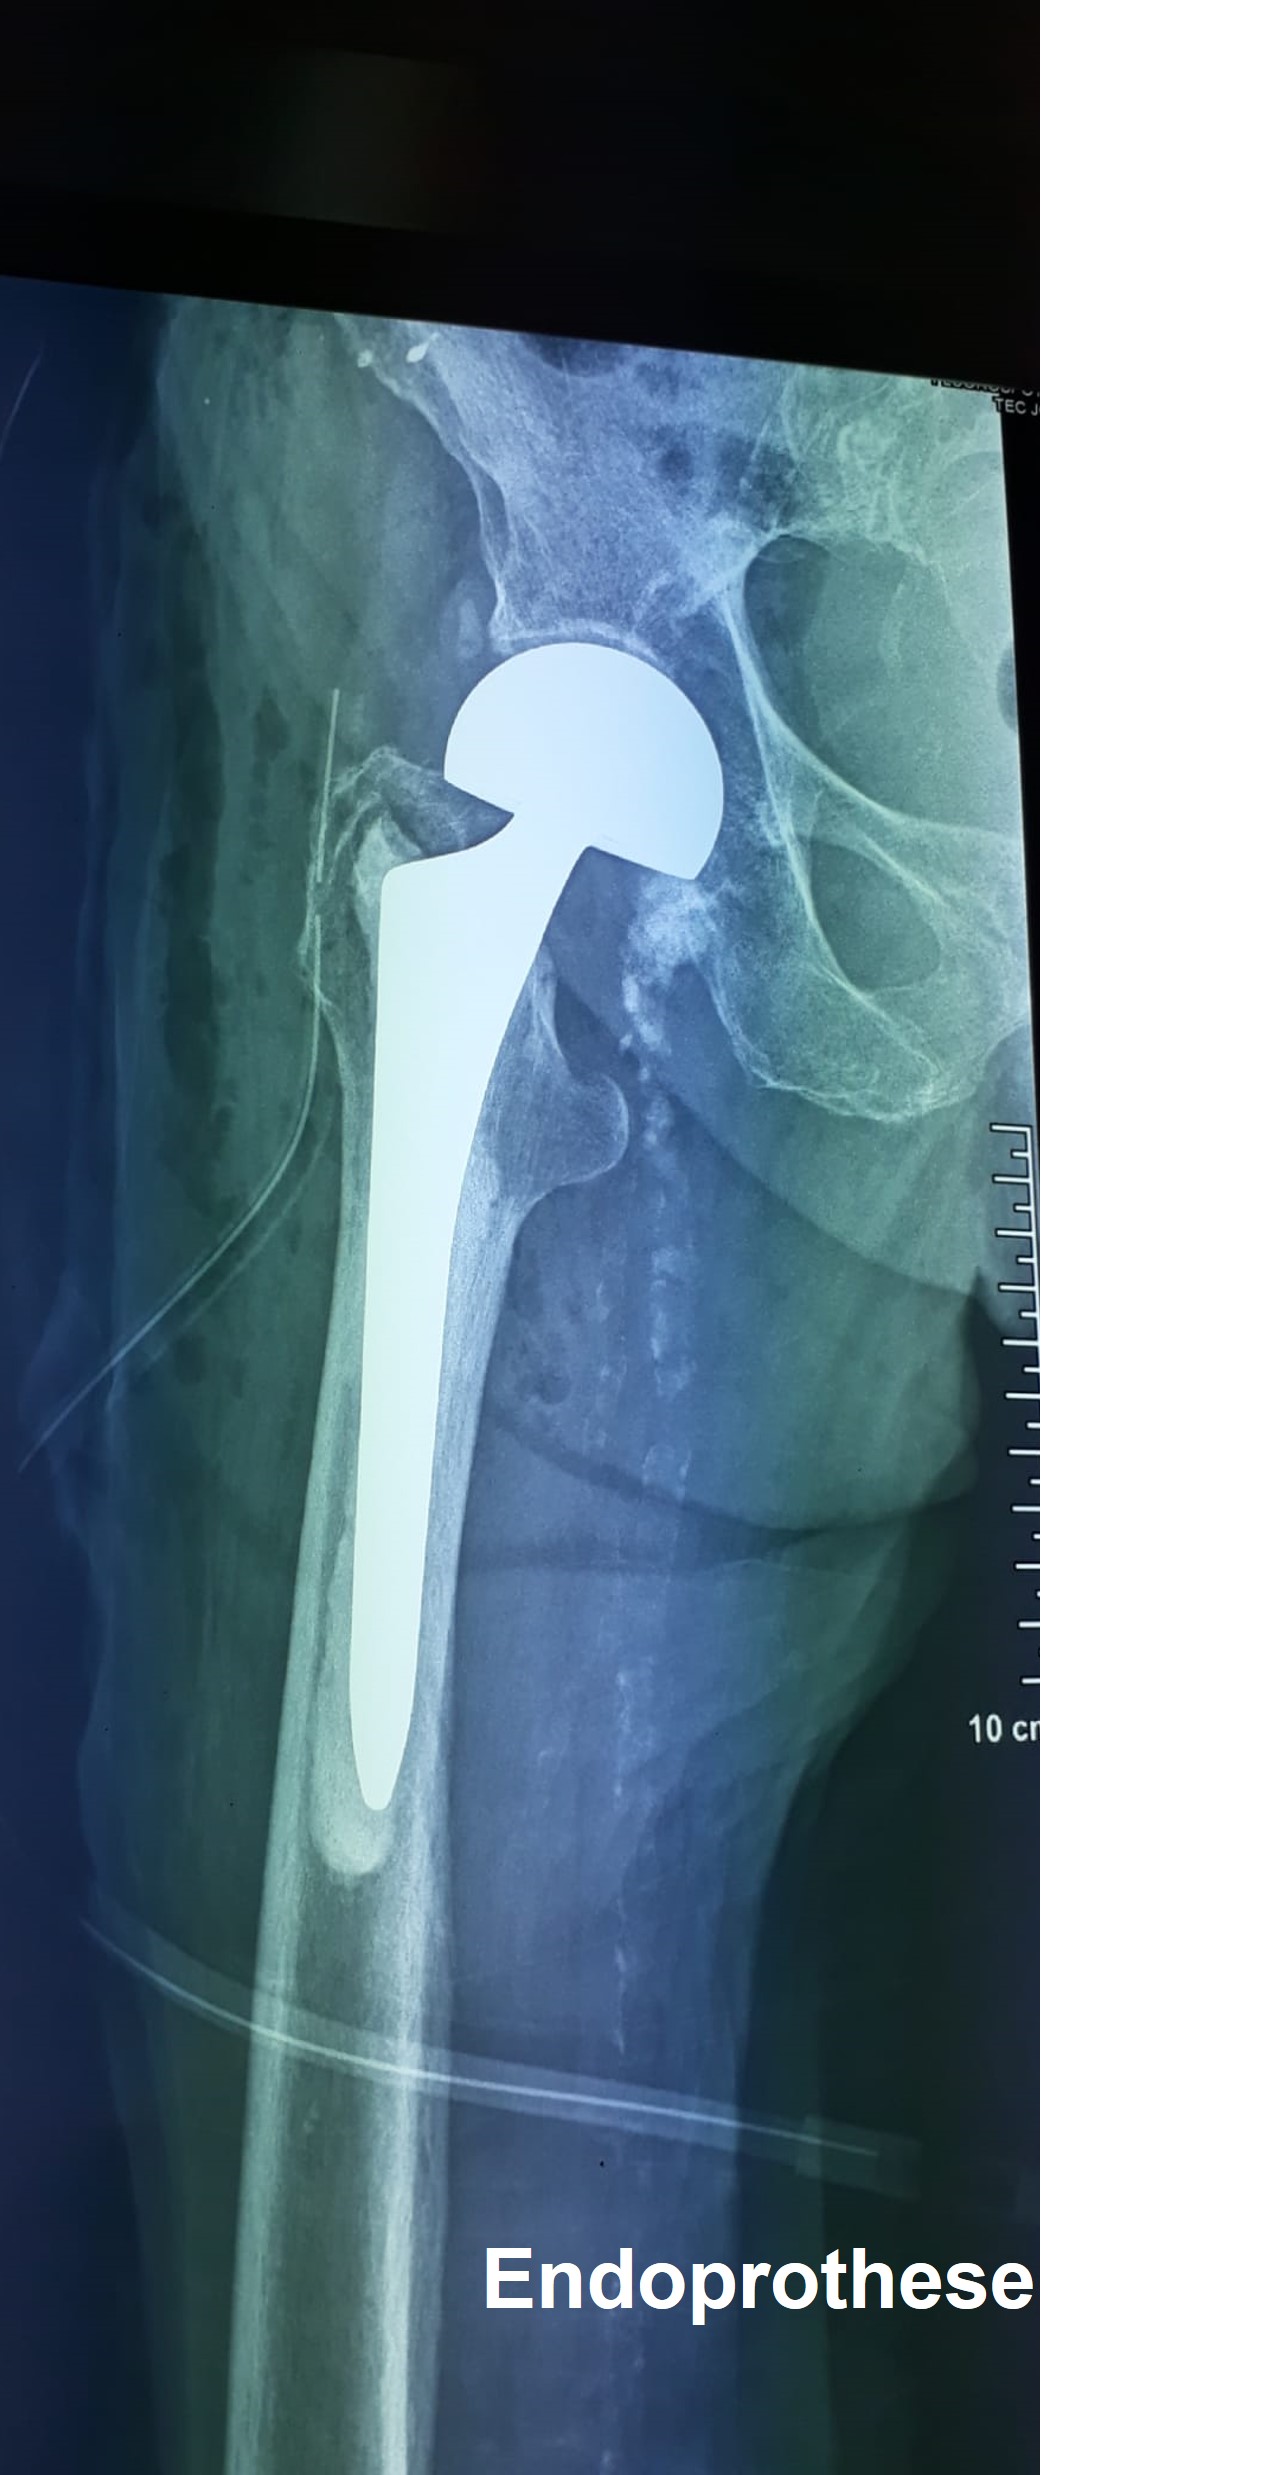

Von Seiten der chirurgischen Kolleginnen und Kollegen wurden verschiedene Operationen begleitet und gemeinsam mit den kapverdischen KollegInnen OP-Techniken und Herausforderungen diskutiert und gemeistert (Drs. Kohlmann / Al-Beyramani / Schirmer). Dabei handelte es sich um 2 Unterschenkelpseu-doarthrosen (die eine mit Nagel, die andere mit Platte und Spongiosaplastik versorgt), eine distale Femurfractur (retrograder Verriegelungsnagel), einen Verrenkungsbruch der Handwurzelknochen (scapholunäre Luxationsfractur) und eine mediale Schenkelhalsfraktur, die mit einer bipolaren Hemiprothese versorgt wurde. Dabei zeigt sich wieder, dass die operativen Fähigkeiten unserer kapverdianischen Kollegen längst mitteleuropäisches Niveau aufweisen, haben doch Dr. Keita und Dr.Tavares ihre jeweils 3 jährige Fachausbildung am Wilhelminenspital (jetzt Klinik Ottakring) absolviert. Das größte Problem ist derzeit der Nachschub und die Logistik der Implantate und Instrumente. Im HAN arbeitet man an einer Lösung. Einige dringende Instrumente (vorallem neue, scharfe Bohrer) haben wir von Cosmas gekauft und mitgebracht. Die Weiterentwicklung der Endoprothetik, der Arthroskopie und den Einstieg in die so dringende Wirbelsäulennotfallchirurgie wollen wir, was die Fortbildung betrifft, besonders unterstützen.